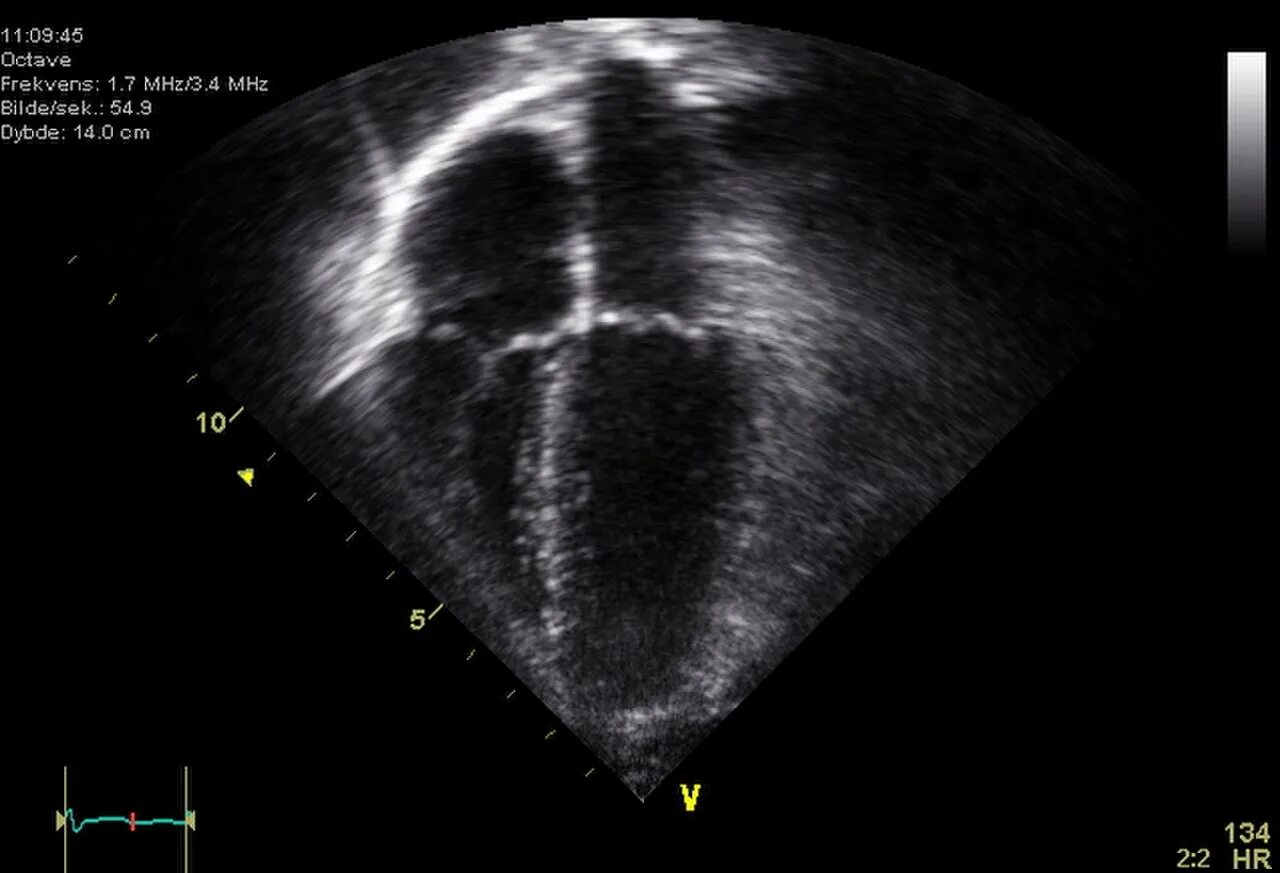

Детское эхо сердца